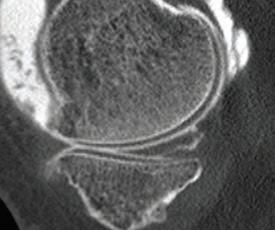

the line? Dr David Colvin 52 Imaging of the knee Dr Gavin Watson 55 Shoulder instability surgery: do it right, do it once Dr William Blakeney 61 A new health paradigm Dr

This magazine has been printed using solar electricity, and the paper is manufactured with elemental chlorine-free pulps. Both printer and paper manufacturer are certified to ISO 14001, the world’s highest environmental standard. 6 Gestational diabetes is serious Dr Emily Gianatti 39 Rule change around medical abortion Dr Alison Creagh 41 Students want more GP time Sarah Bresnehan 60 Brain aneurysms Dr Ruchi Kabra Environment ISO 14001 57 Resurfacing hip joints A/Prof Piers Yates